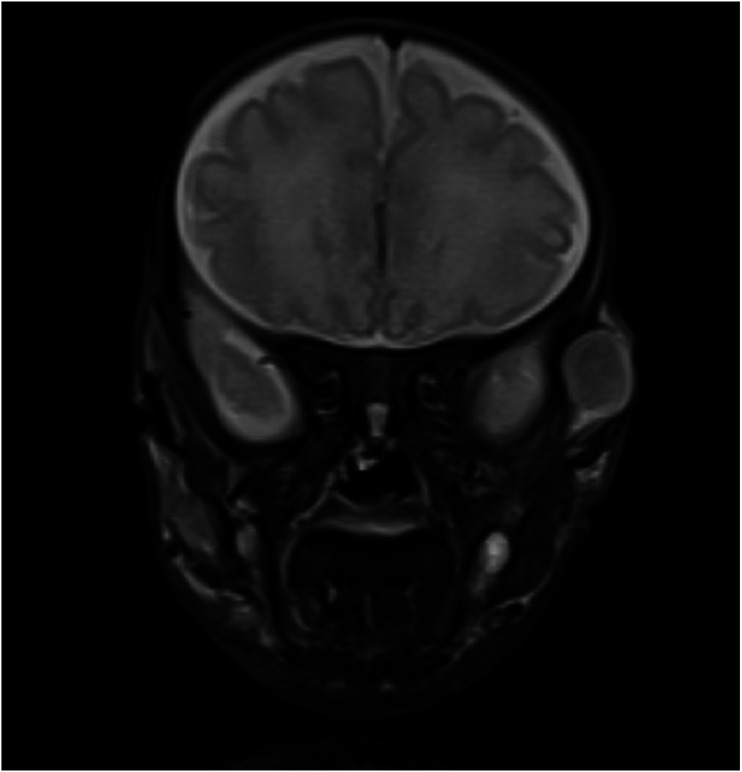

BackgroundInfantile myofibromatosis (IM) is a disorder characterized by proliferation of benign myofibroblastic tumors that typically manifest as solitary or multiple nodules in the skin, muscle, bone, subcutaneous tissues, and visceral organs and can pose significant morbidity and mortality risks, particularly in cases involving visceral organs or causing functional impairment. These soft tissue lesions are the most prevalent benign fibrous tumors that present before age two and can undergo spontaneous regression or are amenable to surgical resection.CaseA preterm, male infant was born via Caesarean section to a mother with a trichorionic, triamniotic pregnancy following preterm labor. Within the first week of life, several well-circumscribed, smooth, non-tender, and soft nodules with some mobility were noticed along the border of the ribs, across the trunk, back, and lower extremities. Ultrasound imaging confirmed well-circumscribed hypoechoic, intramuscular nodules, and biopsy evaluation showed atypical spindle cell proliferation. The biopsied lesion was PDGFRB-mutated on molecular genetic studies, confirming a diagnosis of myofibromatosis. The infant developed mixed lytic and sclerotic deformities of a variety of bones, necessitating treatment given disease progression.ConclusionSuccessful clinical management with low-dose metronomic chemotherapy (methotrexate and vinblastine) is possible and can treat extensive disease, as seen in our patient.

Abstract Image